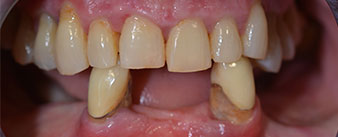

La patiente âgée de 64 ans présente une denture résiduelle des dents 38, 33 et 43 et une prothèse amovible mandibulaire stabilisée par crochets (Fig. 1 et 2).

Dentition résiduelle

Fig. 1

Fig. 2